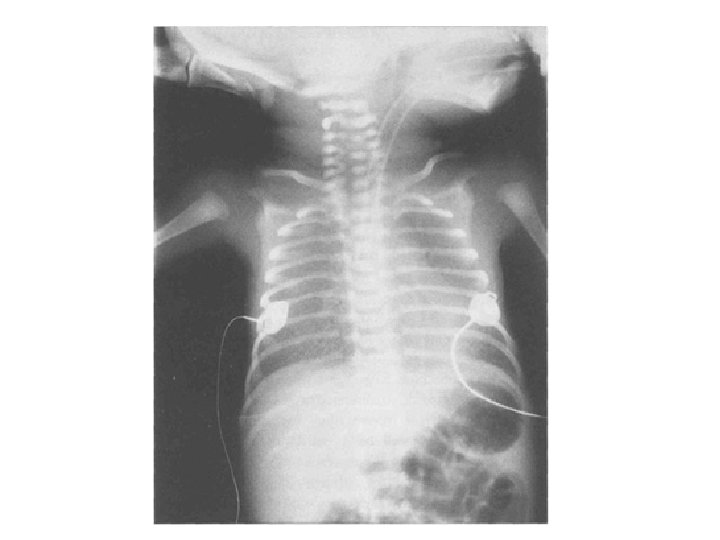

50 с. ж. Легочная ткань не вздута, «диффузная неотчетливость» , нет участков уплотнения (фиброза), локального повышения прозрачности